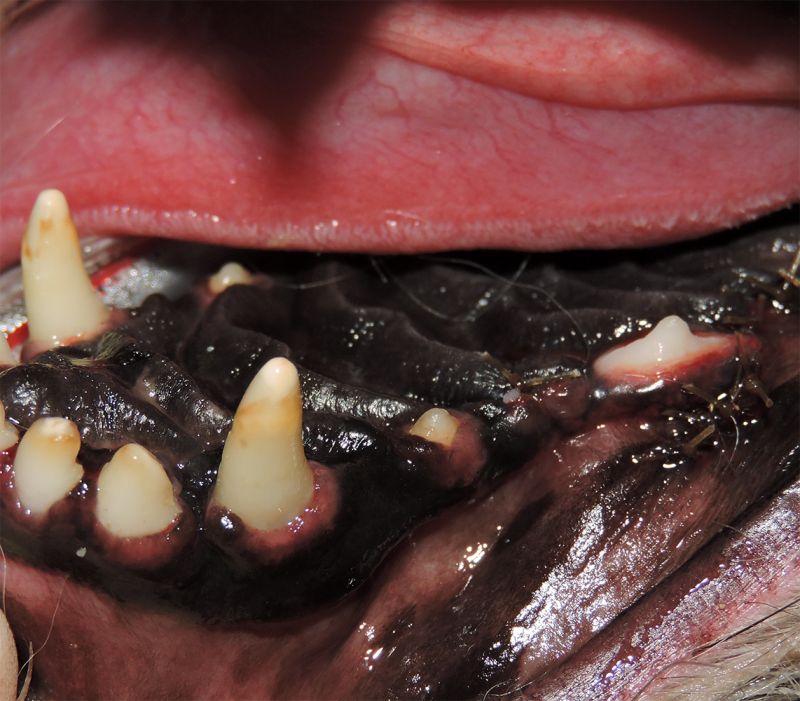

Therapy for Oral Inflammation

Dogs and cats can sometimes have severe inflammation of the mouth and gingivitis. It is not always known what the exact cause of this painful condition is, but it can be successfully managed. In cases of severe inflammation, some or all of the teeth may need to be surgically extracted. This often greatly improves the pain and inflammation in the mouth in over 80% of patients. In severe cases that do not respond to full mouth extractions, medical management can help reduce or resolve the inflammation and pain.